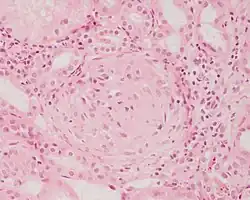

Kłębuszkowe zapalenie nerek (KZN, łac. glomerulonephritis, dawniej choroba Brighta) – grupa chorób nerek, których wspólną cechą jest obecność zapalenia kłębuszków nerkowych[1][2]. Zmiany w pozostałych strukturach nerek (cewkach, miąższu, naczyniach) są wtórnym następstwem zaburzeń w kłębuszkach[1]. Podłożem zapalenia są nieprawidłowe procesy immunologiczne, o charakterze pierwotnym lub wtórnym do innych chorób[1]. Przyczyny pierwotne dotyczą chorób samych nerek (kłębuszków), natomiast wtórne wynikają z innych chorób lub czynników, do których należą: zakażenia, leki, choroby systemowe, nowotwory.